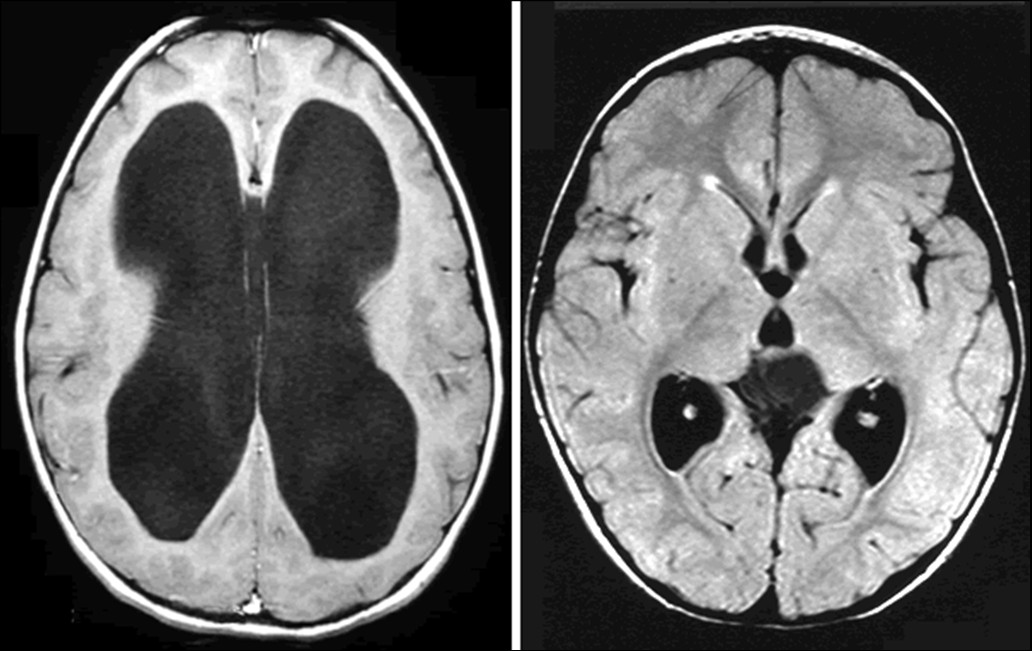

Hemi-megalencefalie (Afwijking ten gevolge van

neurogenese)

Hydra-enceffalie/ porencefalie (Afwijking ten gevolge van

holoprosencefalie

afwijking ten gevolge van neurulatie